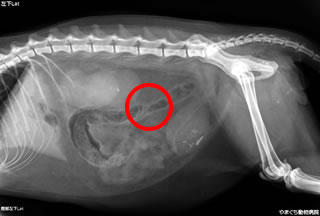

症例:膀胱鏡による結石の除去

膀胱の中に出来た石が原因で、尿道閉塞を何回も繰り返しているとのこと。

また、膀胱切開手術時には憩室に入っていたと思われる結石も確認することができました。